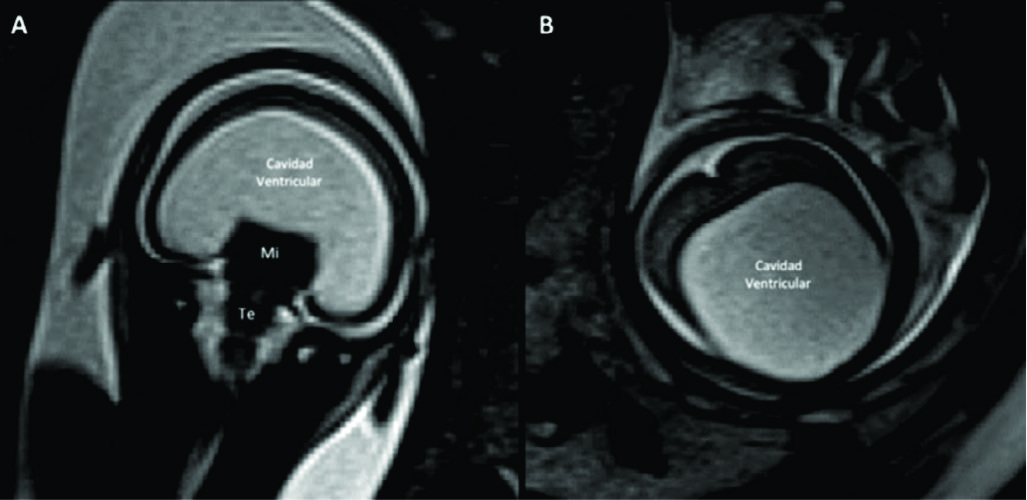

Figura 1

RM Fetal Normal (Edad Gestacional: 27 semanas).

Corte sagital en línea media (A) y corte axial a nivel bi-talámico (B) de cerebro fetal normal en la semana 27 (secuencia rápida T2). En la imagen de línea media se identifica claramente el cuerpo calloso (CC) y la cisura calcarina (è) así como también las estructuras de la fosa posterior con un desarrollo acorde.

En el plano axial se identifica la línea media y la región ganglio-basal con anatomía normal y un patrón gírico acorde a la edad gestacional con un esbozo de cisura silviana (CS).

Los diferentes sectores del sistema ventricular se identifican claramente: ventrículos laterales (VL), 3er ventrículo (situado entre ambos tálamos (T)) y IV ventrículo (situado entre el cerebelo (Ce) y tronco encefálico (Te)).